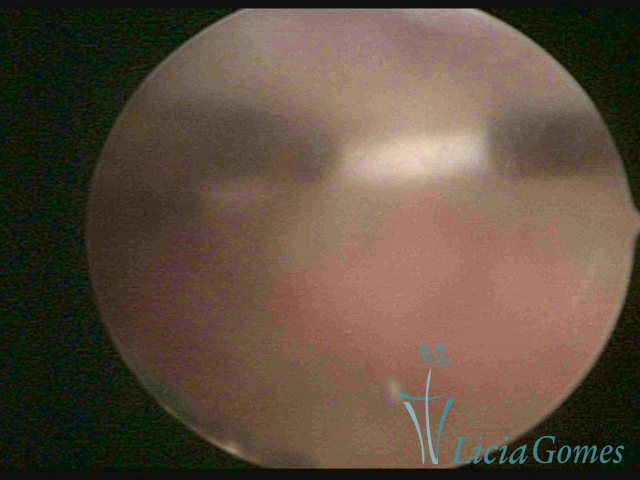

Canal cervical trófico, com o fio de Mirena®